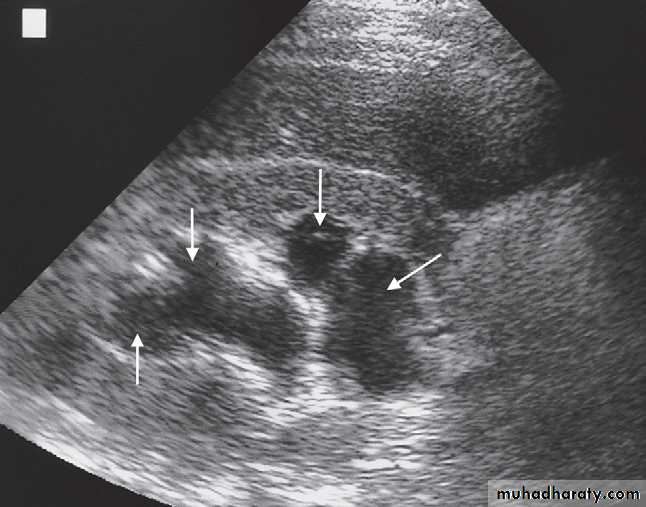

Ultrasound Dilatation of the pelvicaliceal system ( hydronephrosis ) is demonstrated sonographically as a multiloculate fluid collection in the central echo complex, caused by pooling of urine within the distended pelvis and calices .

Major DDX are multiple renal cysts. With prolonged obstruction, thinning of the cortex due to atrophy will be seen.

Some causes of obstruction are identifiable (e.g. carcinoma of the bladder or a stone at the vesicoureteric junction), it is often not possible to determine the cause of urinary tract obstruction at ultrasound examination.